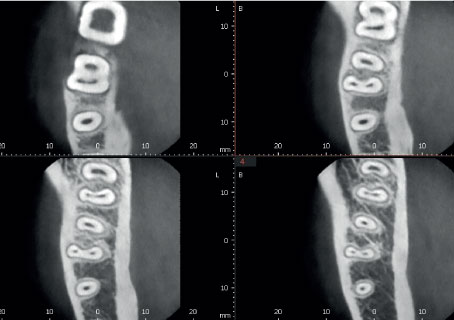

Режим Эндо с высочайшим разрешением

Режим Endo с объемом 4x4 см и размером вокселя 49,5 микрон оптимизирует обработку областей, представляющих повышенный интерес. Он идеально подходит для эндодонтии, поскольку стоматолог может получить изображение с высоким разрешением вокселей.

| ОБЫЧНЫЙ РЕЖИМ | ||||

|

||||

| ENDO РЕЖИМ | ||||